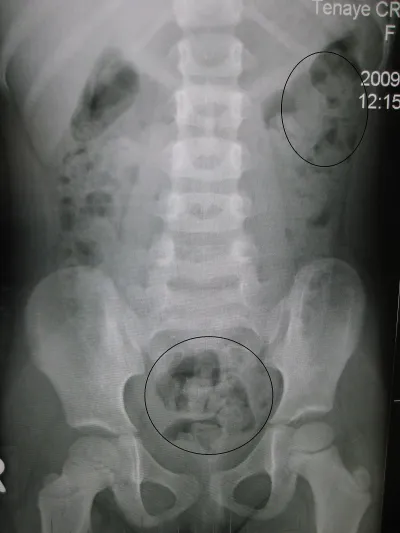

تشخيص الإمساك

معظم الناس لا يحتاجون لاختبارات مكثفة لتشخيص الامساك، فقط عدد قليل من المرضى الذين يعانون من الإمساك لديهم مشكلة طبية أكثر خطورة، و لذلك فإن كنت تعاني من الإمساك لأكثر من أسبوعين فإنه يتوجب عليك مراجعة الطبيب حتى يتمكن من تحديد أسباب الإمساك و مصدر المشكلة و بالتالي تحديد كيفية علاج الامساك .